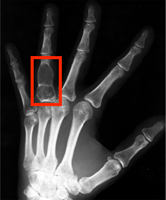

Hand bone age AI

Predict hand bone age. In a small test of 129 random Stanford clinical cases, AI predicted age within 12 months.

C. Fang, S. Baig, D. Larson, M. Fadell, B. Do